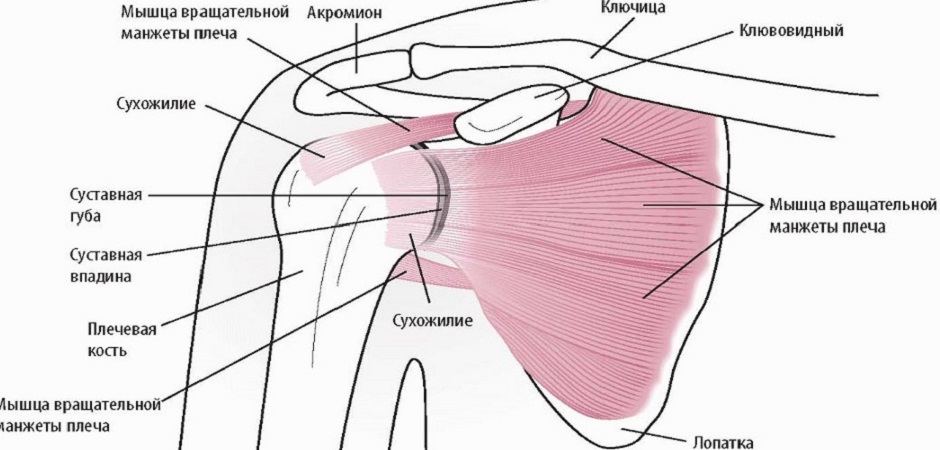

Фотографии поддельтовидной мышцы плечевого сустава

Раздел: Образы вокруг